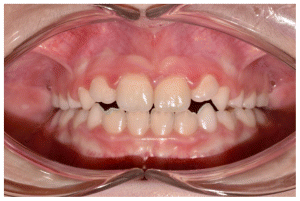

The patient was a young female presenting with a Class III dento-skeletal malocclusion, which was treated using the AMCOP® TC appliance. A comprehensive diagnostic protocol was carried out both before and after treatment, including orthopantomography (Figure 2–3), postero-anterior teleradiography (Figures 4, 5), latero-lateral cephalometric radiography (Figures 6, 7), cephalometric analysis (Tables 1, 2), as well as extraoral (Figures 8, 9) and intraoral photographs (Figures 10, 11). The extraoral examination revealed an edge-to-edge incisal relationship and the presence of a midline diastema. Pre-treatment cephalometric analysis (Deltadent® Lana, Bolzano, Italy) confirmed the diagnosis of a skeletal Class III malocclusion. The treatment plan involved the use of the AMCOP® TC appliance. The patient was instructed to wear the device for two hours in the afternoon and throughout the night for the first six months, followed by nighttime use only for an additional six months. Upon completion of the treatment, the patient achieved a Class I occlusion, with correction of both overjet and overbite. Additionally, the device facilitated tongue re-education and contributed to the postural realignment of the first cervical vertebra.